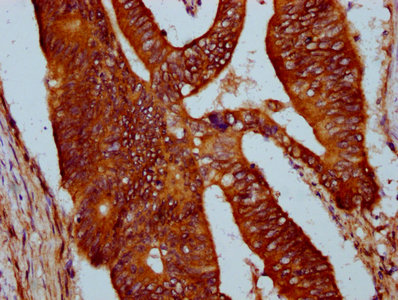

IHC image of CSB-PA732939LA01HU diluted at 1:400 and staining in paraffin-embedded human pancreatic cancer performed on a Leica BondTM system. After dewaxing and hydration, antigen retrieval was mediated by high pressure in a citrate buffer (pH 6.0). Section was blocked with 10% normal goat serum 30min at RT. Then primary antibody (1% BSA) was incubated at 4°C overnight. The primary is detected by a biotinylated secondary antibody and visualized using an HRP conjugated SP system.

IHC image of CSB-PA732939LA01HU diluted at 1:400 and staining in paraffin-embedded human colon cancer performed on a Leica BondTM system. After dewaxing and hydration, antigen retrieval was mediated by high pressure in a citrate buffer (pH 6.0). Section was blocked with 10% normal goat serum 30min at RT. Then primary antibody (1% BSA) was incubated at 4°C overnight. The primary is detected by a biotinylated secondary antibody and visualized using an HRP conjugated SP system.